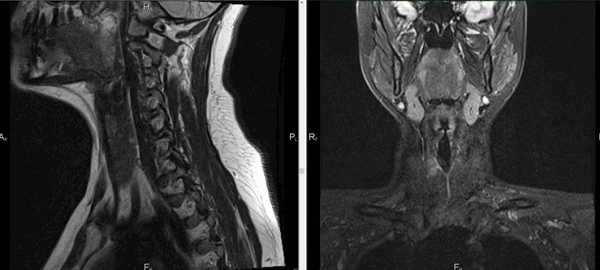

Онкологический процесс на томограммах щитовидной железы

МРТ противопоказана на ранних сроках беременности. Контрастирование запрещено вне зависимости от периода гестации. Не используют раствор гадолиния у пациентов, страдающих тяжелыми патологиями печени и почек. Причиной служит усиление нагрузки на органы фильтрации в процессе выведения препарата.

Видно ли на МРТ рак щитовидной железы?

Благодаря резонансному движению заряженных частиц в ответ на воздействие магнитного поля метод визуализируют структурное перерождение тканей, изменение формы, размеров, контуров сканируемого органа. Послойные фотографии, сделанные в аксиальной, фронтальной и сагиттальной проекциях, отображают малейшие трансформации щитовидной железы, включая патологии кровеносных сосудов.

Основными признаками злокачественной опухоли на МРТ являются:

неоднородная структура образования, наличие кист и кальцинатов;

размытый ореол вокруг опухоли (что свидетельствует о перифокальном отеке паренхимы железы);

отсутствие четкой границы между пораженными и здоровыми тканями, инфильтрация атипичных клеток в окружающие структуры;

особенности кровообращения: собственная сеть сосудов представляет собой сложную запутанную систему с большим количеством анастомозов.

Контрастная МРТ при раке щитовидной железы показывает медленное накопление индикатора, что является признаком малигнизации (озлокачествления) образования.

Метод отражает состояние окружающих тканей, позволяет выявить как первичное образование, так и метастазирование опухоли в регионарные лимфатические узлы, загрудинную область, ткани шеи. Точную локализацию очага и степень прорастания атипичных клеток в соседние структуры устанавливают при помощи трехмерного изображения сканируемой зоны.